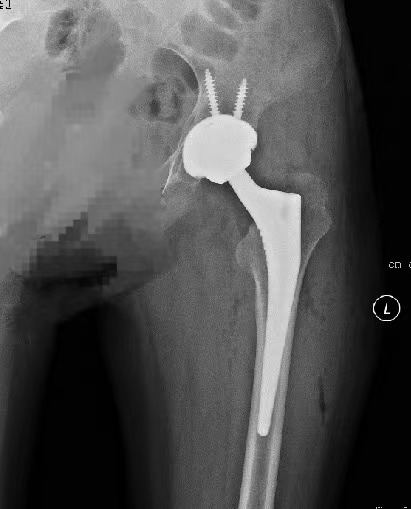

女子股骨头坏死,险些致残。通过市立医院本部关节置换,日前她终于重新“站了起来”。

要解决走路剧痛等日常生活问题,置换髋关节是最直接也最有效的办法。陈广祥告诉她,人工髋关节置换是一种临床上已经比较成熟的手术,手术时间短、见效快。

在医生的建议下,小金接受了快速康复手术。第二天走路时,她髋关节的痛感果然就消失了。